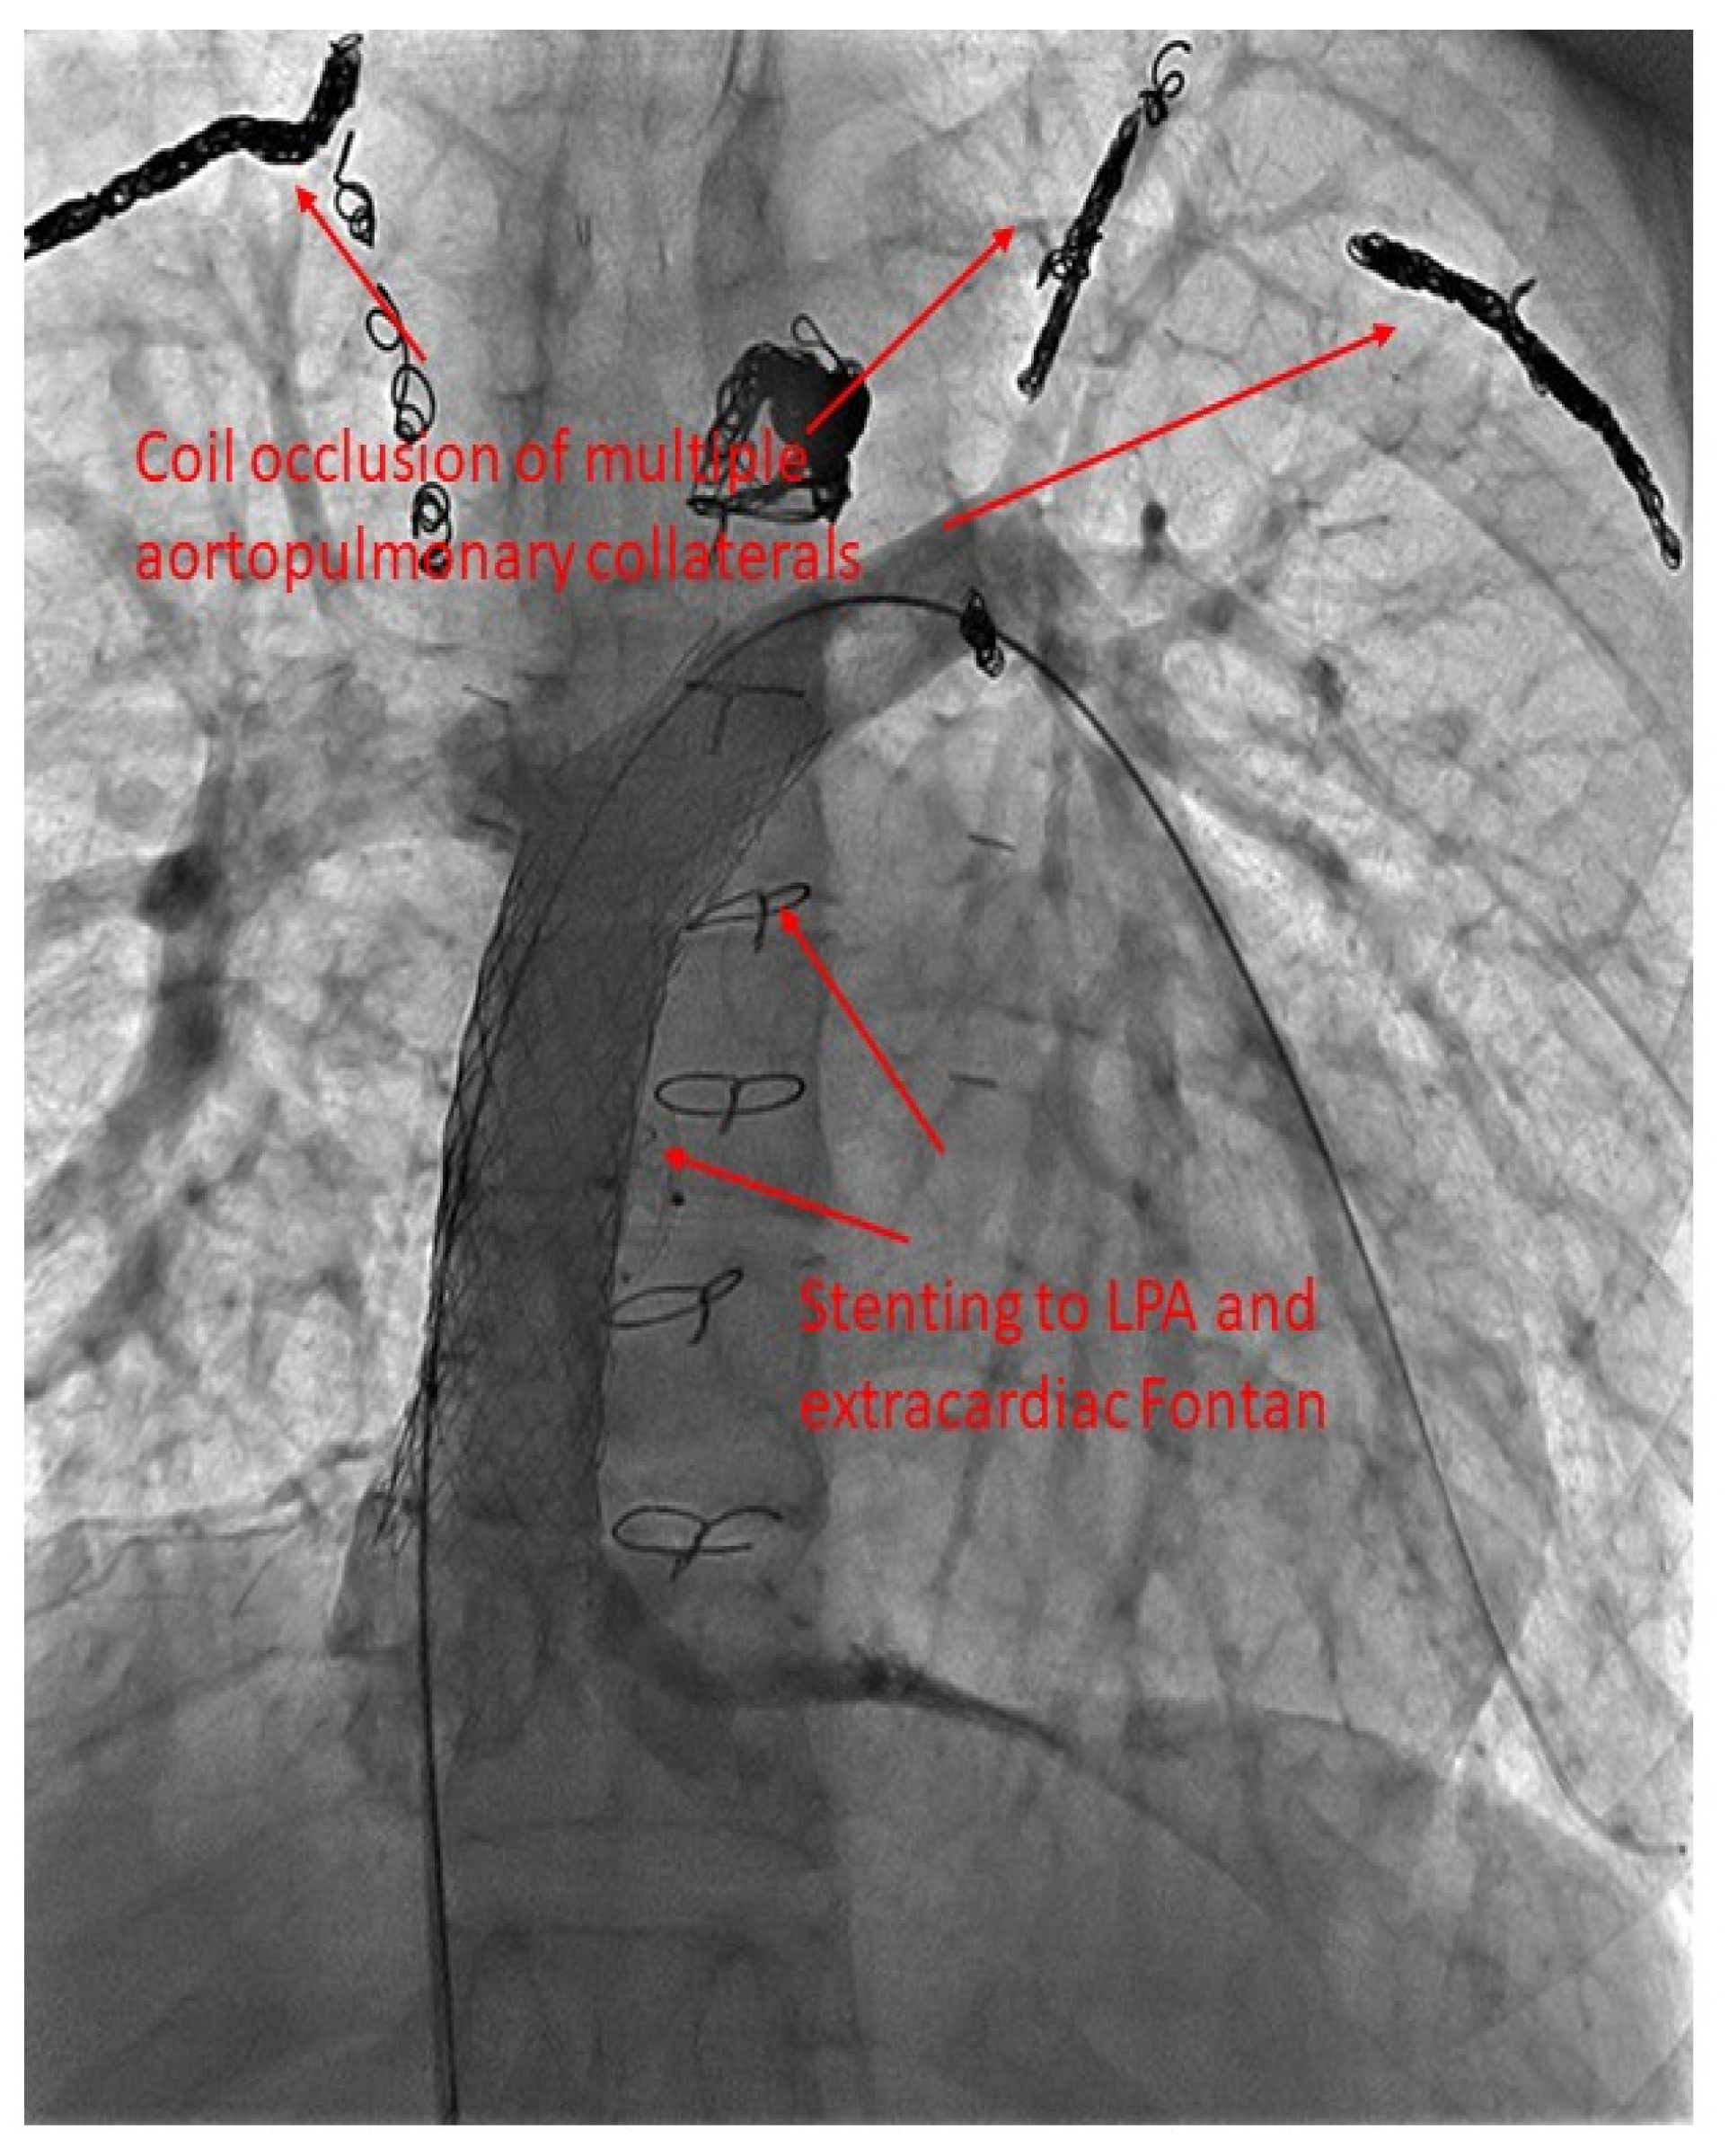

27. Liver Lymphatic Embolization (LLE)

30. Collateral Vessels

- Dori, Y.; Glatz, A.C.; Hanna, B.D.; Gillespie, M.J.; Harris, M.A.; Keller, M.S.; Fogel, M.A.; Rome, J.J.; Whitehead, K.K. Acute effects of embolizing systemic-to-pulmonary arterial collaterals on blood flow in patients with superior cavopulmonary connections: A pilot study. Circ. Cardiovasc. Interv. 2013, 6, 101–106. [Google Scholar] [CrossRef] [PubMed]

- Tan, W.; Reardon, L.; Lin, J.; Lluri, G.; Venkatesh, P.; Bravo-Jaimes, K.; Biniwale, R.; Van Arsdell, G.; Ponder, R.D.; Aboulhosn, J. Occlusion of aortopulmonary and venovenous collaterals prior to heart or combined heart-liver transplantation in Fontan patients: A single-center experience. Int. J. Cardiol. Congenit. Heart Dis. 2021, 6, 100260. [Google Scholar] [CrossRef]